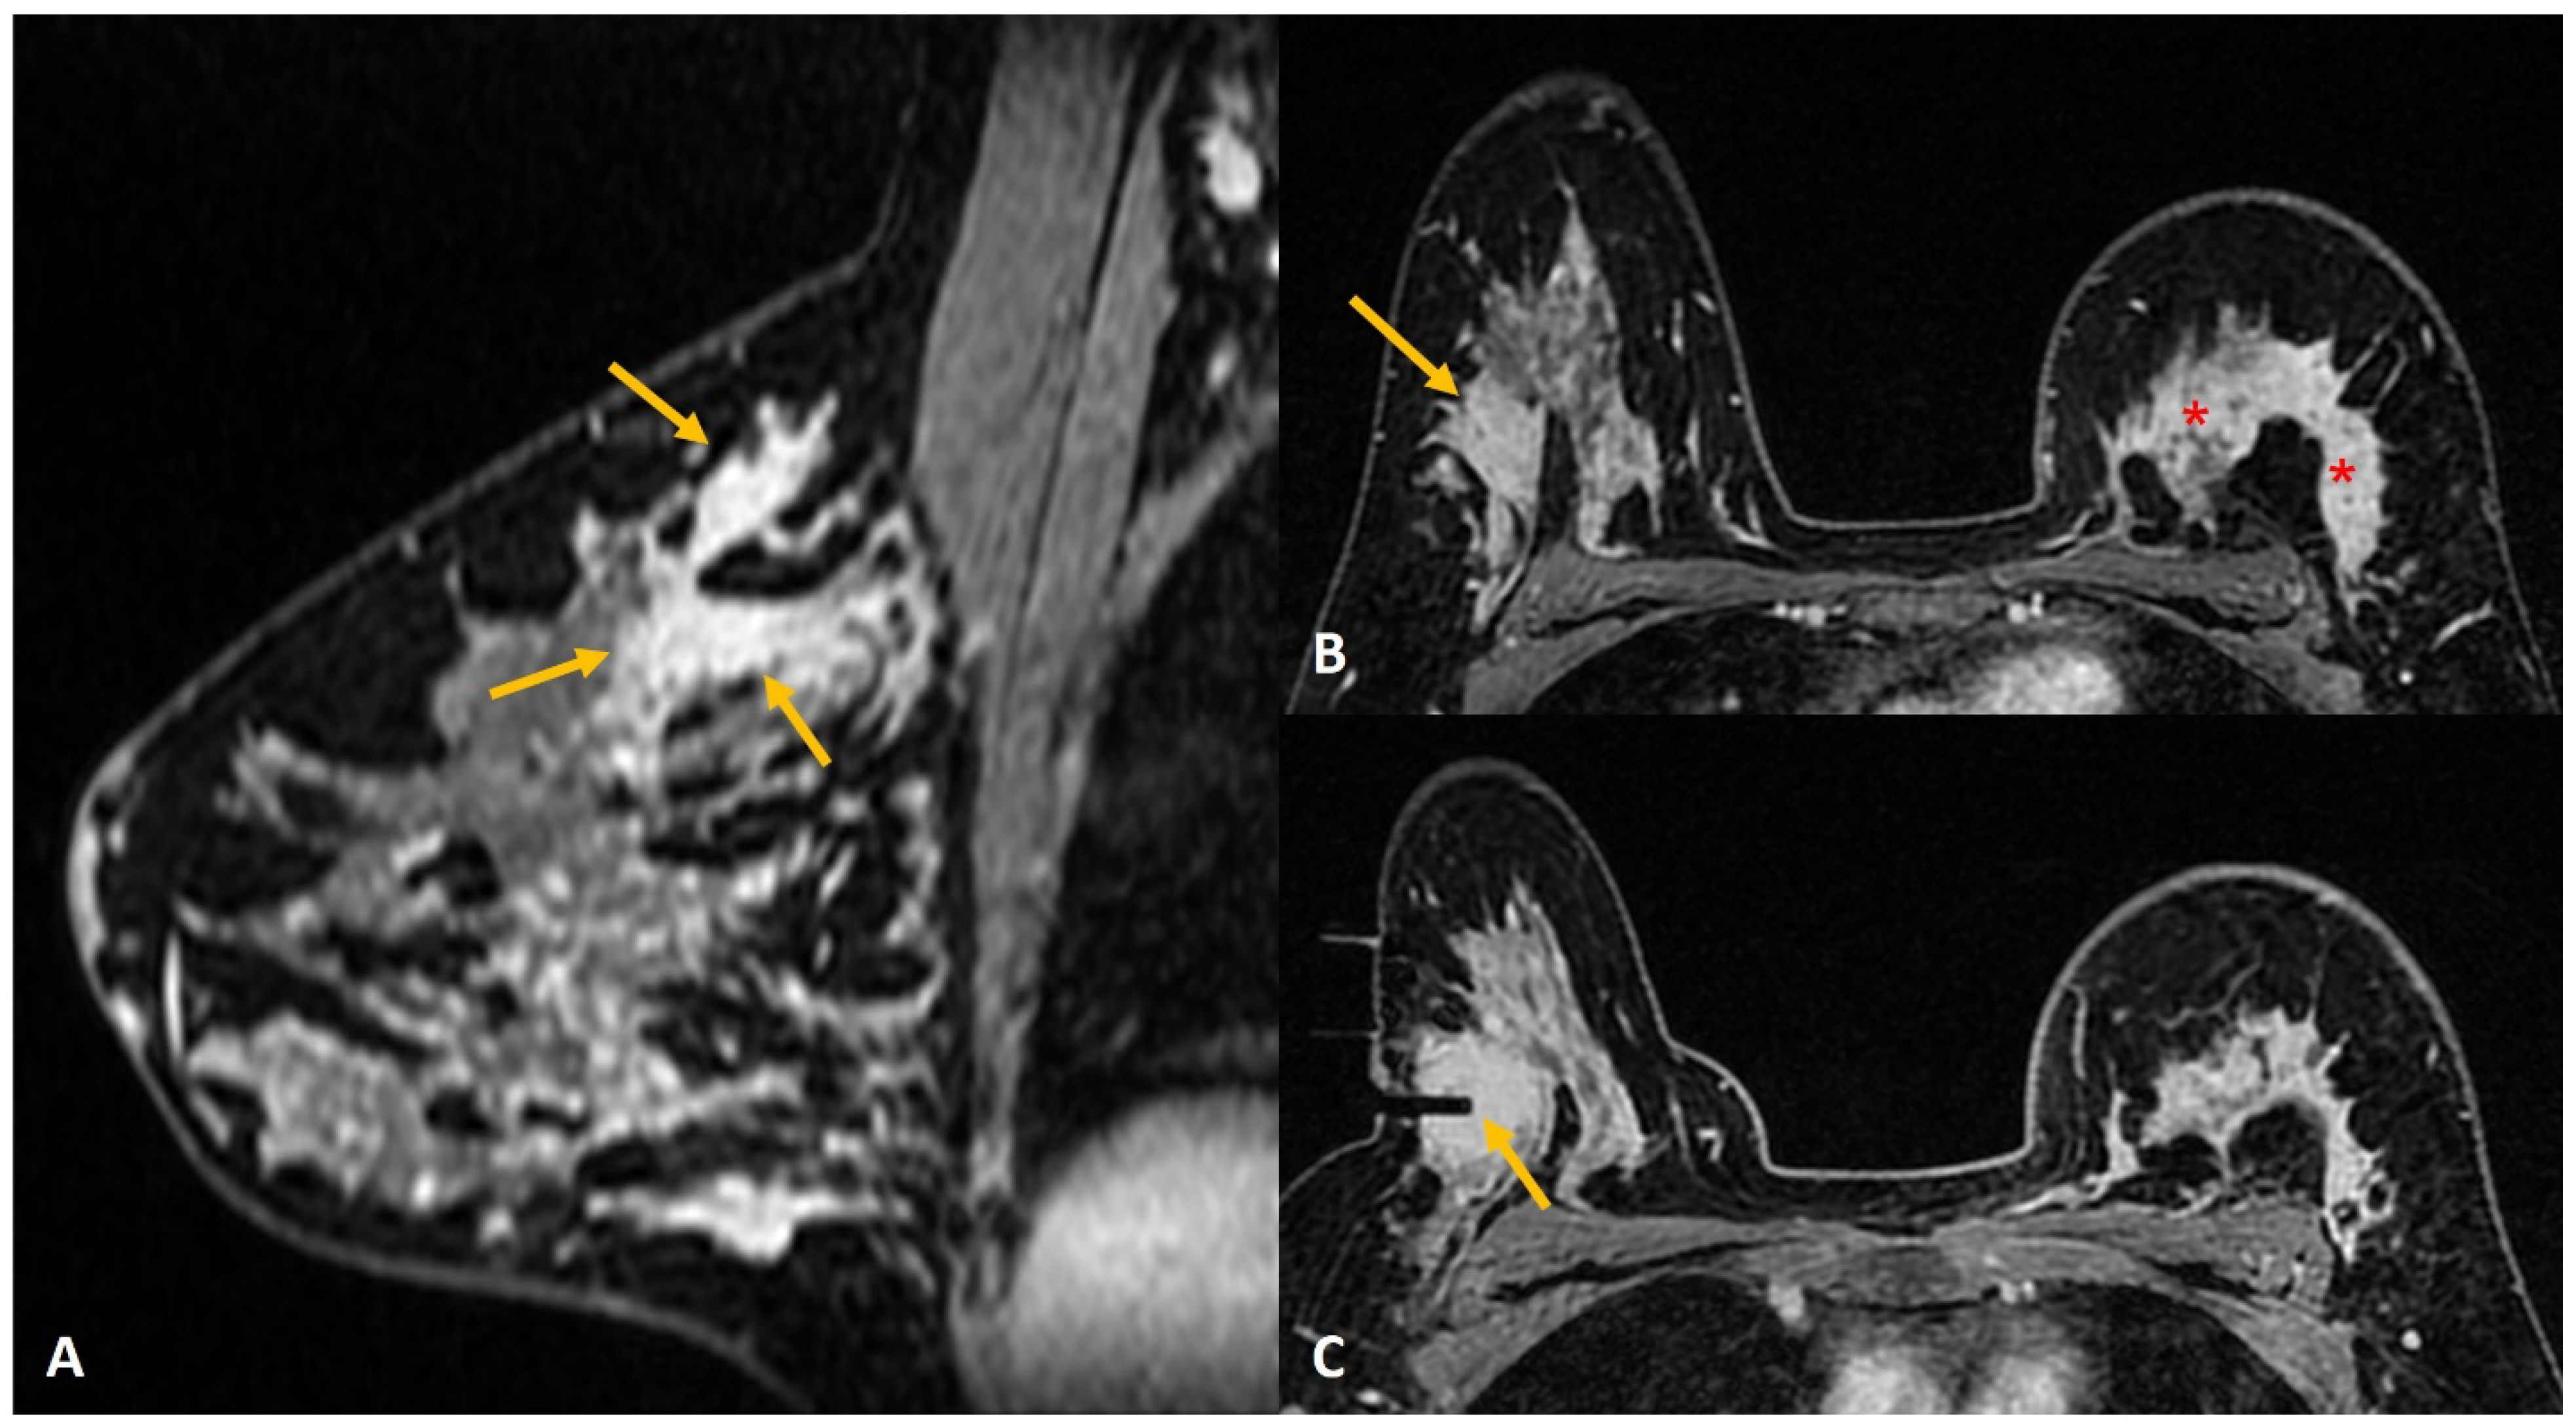

Figure 1.

A 36-year lactating mother diagnosed with left breast inflammatory breast cancer underwent staging MRI. (A). Sagittal post contrast T1w fat-saturated image showed a segmental non-mass enhancement (yellow arrows) in the upper outer quadrant of the right breast. This was also distinctly FDG avid on PET scan (not shown here). (B). Axial staging scan showed diffusely enhancing mass in the left breast correlating with known cancer (red asterisks). Segmental non-mass enhancement was also seen in upper outer quadrant of the right breast (yellow arrow). (C). MRI-guided biopsy shows the tip of the obturator in correct location with surrounding post-biopsy hematoma (yellow arrow). Histology was reported as fibrocystic change.